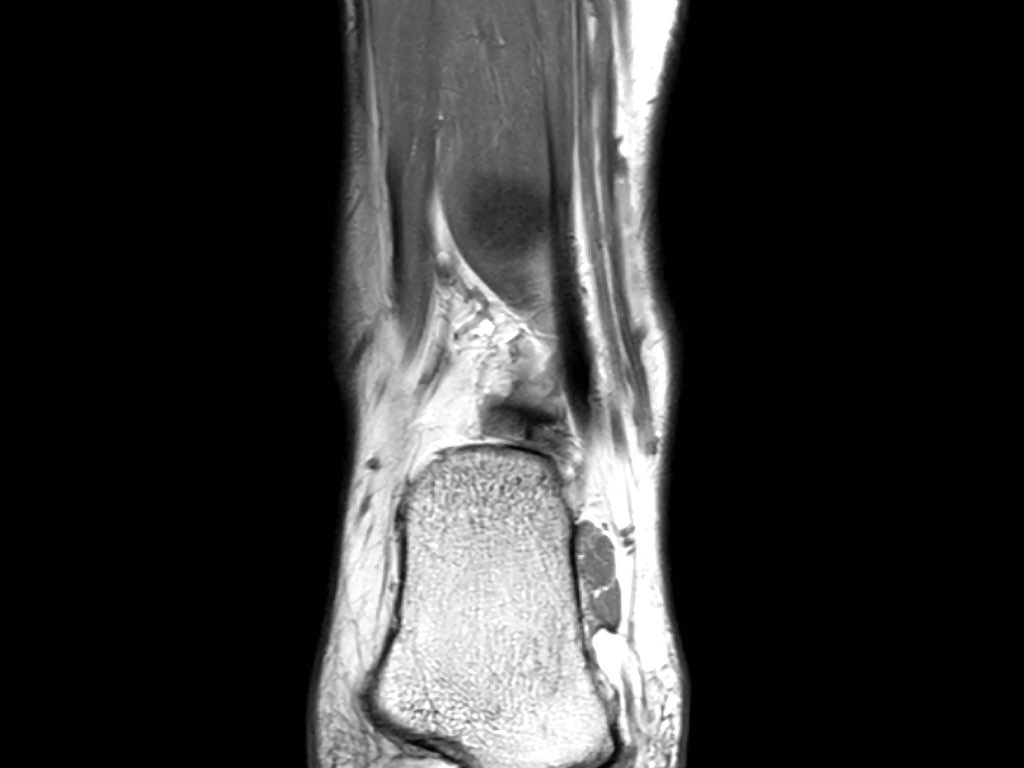

Cuộn qua các ảnh cắt vành.

Bạn có thể phóng to ảnh bằng cách nhấp vào.

Đây là hình ảnh của ba bệnh nhân có tổn thương dây chằng ATFL.

Bệnh nhân bên trái có phù nề nhẹ xung quanh dây chằng ATFL, trong khi bản thân dây chằng trông bình thường.

Đây có thể là căng dây chằng mức độ nhẹ (độ 1).

Thường được nhận thấy rõ nhất trên ảnh có kỹ thuật ức chế mỡ (fatsat).

Bệnh nhân ở giữa có dày lên và rối loạn cấu trúc, biểu hiện của rách một phần (độ 2).

Bệnh nhân bên phải có rách toàn bộ chiều dày (độ 3).